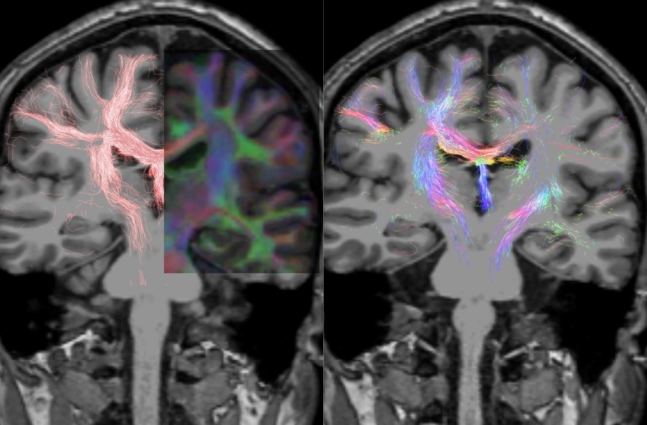

Foto: Luis Concha Loya

En México está subutilizada la resonancia magnética funcional (fMRI, por sus siglas en inglés), técnica que mide la actividad cerebral por medio de la detección de cambios en el flujo sanguíneo; es clave para la investigación, la precisión diagnóstica y la intervención de enfermedades del cerebro, como el Parkinson.

Otro punto a favor es que los equipos actuales han alcanzado una calidad tan alta que proporcionan “un nivel exquisito de detalle” de las diferentes estructuras cerebrales, como el grosor de la corteza, el nervio óptico y el cerebelo. También indica la conectividad cerebral a partir de ciertos estímulos.

La resonancia magnética funcional opera bajo el principio de que cuando una región del cerebro se activa necesita más oxígeno para alimentar a las neuronas en funcionamiento. Este cambio en la demanda de oxígeno causa un aumento en el flujo sanguíneo hacia esa área, lo que se puede detectar con un escáner de fMRI.